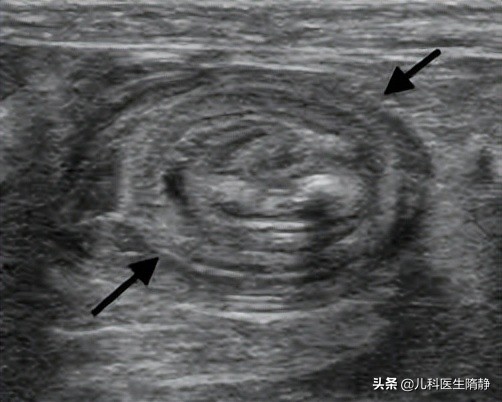

根据肠套叠的特征性影像,B超在肠套叠横断面上显示为“同心圆”或“靶环”征,纵切面上,呈“套筒”征。